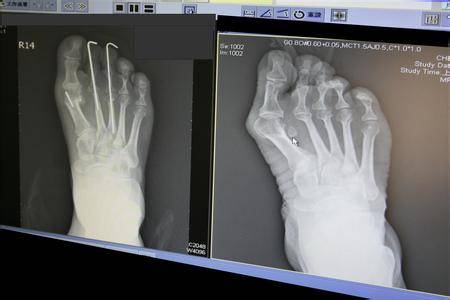

在2011年的时候,贝嫂就因非常严重的脚拇指外翻被专业医生要求放弃高跟鞋,但是她没有听。

常年喜欢穿20多厘米的高跟鞋的习惯也让贝嫂的脚再也招架不住了。直到今年,她才正式地把医嘱提上了日程。

和贝嫂一样,受拇指外翻困扰的女星还有杨紫琼。有一次被媒体拍到了穿平底鞋的照片,拇指外翻非常严重。

拇指外翻不仅影响美观,而且会持续疼痛,严重的时候无法走路。

三十几岁时的徐若瑄,也曾接受手术治疗拇指外翻,她曾透露自己前前后后做了四次手术,还耽误了专辑的发表。